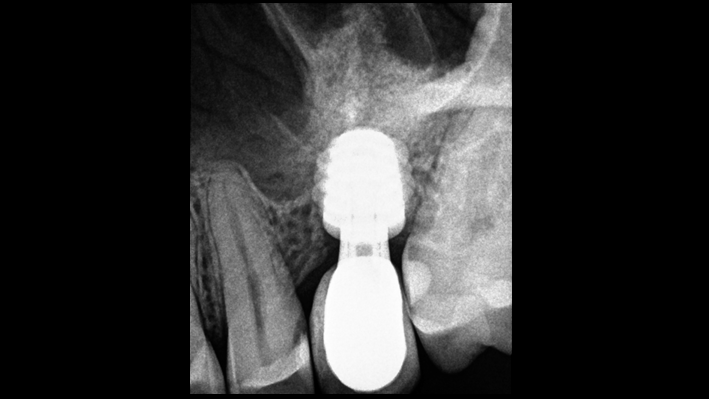

Clinical case: # 46 implant placement & GBR using i-Gen membrane for significant vertical resorption & mixed bone defect

- Courtesy of Dr. Iulian Filipov, Romania -

Keywords

AnyRidge, mandibular posterior, i-Gen, resorption, bone defect, bone regeneration, space management, #46, GBR, Dr. Iulian Filipov

Products:

AnyRidge implant system, i-Gen

“AnyRidge KnifeThread achieves excellent stability in regenerated bone & even in only 3mm bone height!”